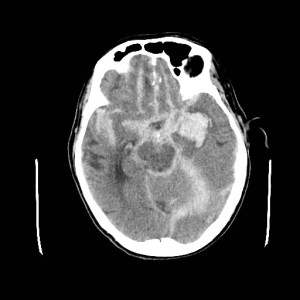

Grado 4- Coagulo intracerebral o intraventricular con HSA difusa o sin ella.